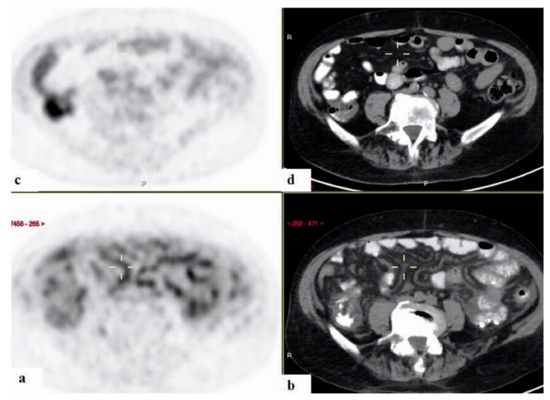

3.3. Contribution of 18FDG-PET/CT to FUO Workup

3.4. 18FDG-PET/CT Contributiveness According to Disease Category